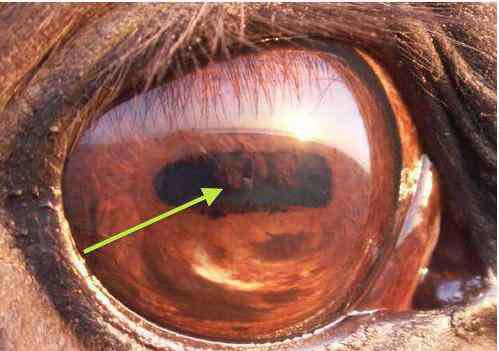

当前,我国各年龄段青少年的近视呈现发病年龄早、进展快、程度深的趋势。据不完全统计,我国小学生近视发病率约30%、初中生约60%、高中生约80%,而大学生已高达90%。户...